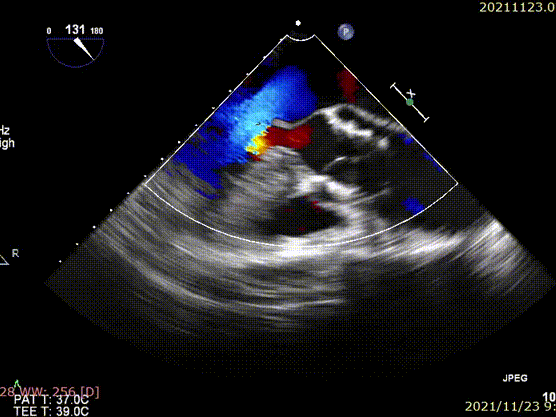

心脏彩超:重度PNAR(三叶瓣),轻度MR,中度TR,左室舒张末内径53mm,左室收缩末内径35mm,左室射血分数(LVEF)为62%。

术前超声